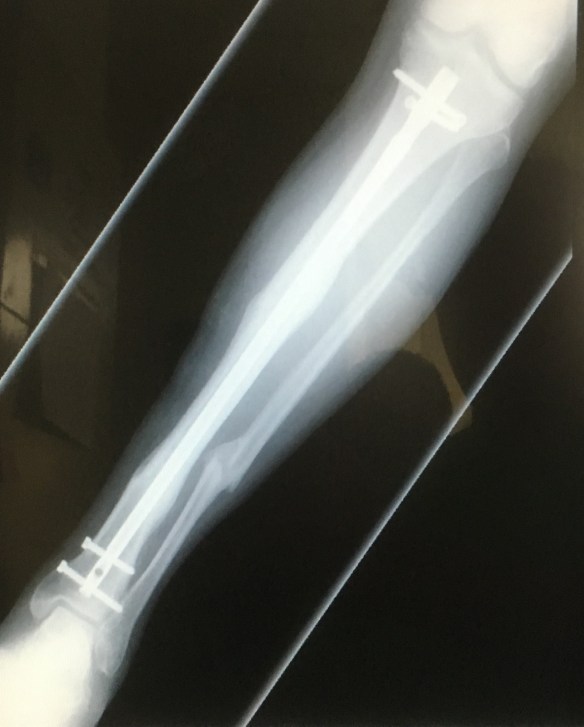

You may recall that in 2015, Jeffrey pedaled us 1000 miles through New England despite a painful broken leg.

Ten days before the 2015 Ride. Three partly healed breaks.

In 2016, Jeffrey pedaled us 1400 miles from Chicago to Albuquerque despite four irritating screws.

Two of the screws removed after the 2016 Ride. The rod remains.